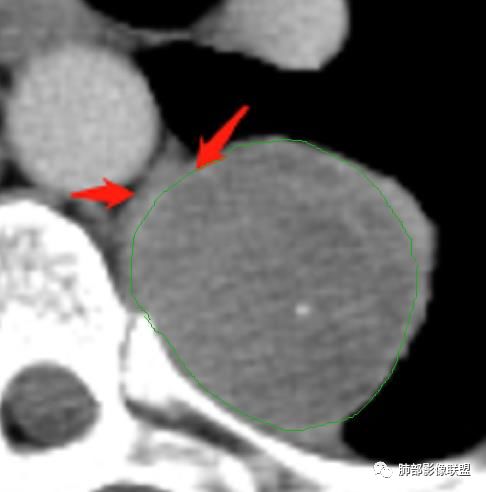

曹志勇:右肺尖后段类圆形病灶,边界清边,缘锐利,宽基底与胸膜相连,环形强化,内似见蛇纹血管征,考虑胸膜孤立性纤维瘤,右肺外底段病灶,考虑炎性可能大

张帅:患者中年男性,咳嗽 咳痰3月,痰为白色粘痰,左上肺病灶,边缘光滑,周围未见毛刺 分叶,肺组织受挤压,与胸膜关系密切,部分层面与胸膜脂肪间隙消失,有胸膜尾征,病灶定位于胸膜,病灶增强可见强化,边缘可见增强血管,内可见低密度区,考虑 孤立胸膜纤维瘤?神经鞘瘤?右肺下叶外基底段病灶,病灶与胸膜有牵拉,病灶边缘光滑,平直 u型征,未见明显毛刺,增强病灶内可见增强血管影,边缘低密度,考虑病灶内存在痰栓。右下肺病灶考虑良性炎症性病灶,ABPA?

李志国:左侧椎旁团块,宽基底、胸膜掀起,定位肺外,增强轻度强化,有蛇纹血管征,考虑孤立性纤维瘤,鉴别神经源性肿瘤

薏米:左下近脊柱旁可见一结节状密度增高影,肺外,边界清,边缘规整,无分叶,无毛刺,无棘突,宽基底与胸膜相连,不均匀轻度强化,考虑为良性病变,神经源性可能性大,为神经鞘瘤,鉴别孤立性神经纤维瘤,神经节瘤,右肺片装密度增高影,考虑为炎症可能性大

张小兵:老年男性,慢性病程,咳嗽咳痰3月,左下肺脊椎旁沟区见宽基底类圆形软组织肿块,无分叶,瘤肺境界光整,其内见点状钙化,周边肺组织挤压,胸膜尾征,延迟强化,提示内含纤维成分,考虑神经源性肿瘤,SFT可能。右下肺病灶收缩力强,内见扩张支气管,提示慢性炎症,考虑机化。

是这样,如果是胸膜来源的SFT,在脊柱和病灶之间应该会有脂肪层,但是这个脂肪层没有,所以不太考虑SFT,支持神经鞘瘤。而且供血看不清,似乎是这个。

感谢:@王军辉-蓟州区医院 影像?我看应该是包膜

M-Imaging :有完整的壁

丽:有包膜

M-Imaging :包膜有强化

嗜酸性粒细胞:是包膜还是血管哦

平安是福:平扫31Hu,动脉期33–42Hu,静脉期,39–54Hu。

1.左上胸内脊柱旁半圆形肿块,质地坚实,密度比较均匀。

2.病灶周边见胸膜掀起,应当考虑胸壁或是纵隔来源,肺内病变不会如此。

7.静脉期轻度强化,注意不是环形强化,亦未显示明确的“AB区”,神经鞘瘤与副节瘤亦未找到支持点。